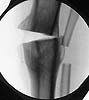

intraop